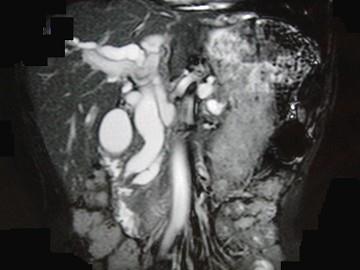

问题 患者男,47岁,进行性黄疸,发热,腹胀,影像检查如图,最可能的诊断是 ( )

选项 A、十二指肠壶腹癌 B、胰头癌 C、胆总管结石 D、胆总管癌 E、胆总管囊肿

答案 A